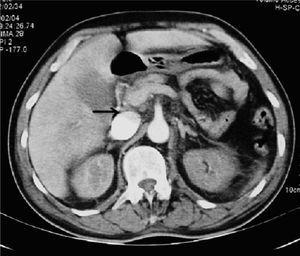

Varón de 62 años con antecedentes médicos de hipertensión arterial, resección transuretral de próstata hace 2 meses e infecciones urinarias de repetición tratadas con ciprofloxacino. Es intervenido de forma programada de adenocarcinoma de próstata, realizando resección prostática radical ampliada. Al cuarto día de postoperatorio presenta hipotensión arterial, oliguria, alteraciones de la coagulación compatibles con coagulación intravascular diseminada, y brusca disminución del hematocrito y de la hemoglobina (24% y 7,5 g/dl respectivamente). Es ingresado en la Unidad de Cuidados Intensivos (UCI) precisando perfusión de noradrenalina, trasfusión de 3 concentrados de hematíes, plaquetas y plasma fresco congelado, siendo intubado a las pocas horas de su ingreso tras disnea brusca. Se realizó tomografía axial computarizada toraco-abdominal de urgencia apreciando restos sanguíneos en vejiga y trombosis de eje esplenoportal y de vena ilíaca primitiva izquierda (figs. 1 y 2). Se implantó filtro en la vena cava inferior, una vez corregidas las alteraciones de la coagulación.

Figura 1

Figura 2